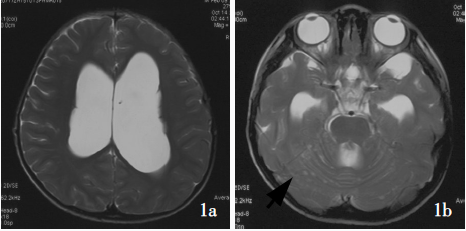

DNT在MRI T1加权像上表现为低信号,在MRI T2加权像上表现为高信号。病灶基于皮质,并局部扩张皮质,有时会延伸入白质。增强表现各异,发生于不到1/2的病例;增强为斑片状、多灶性,而非弥漫性增强。因肿瘤生长缓慢,邻近病灶的颅骨有时变形。

图:DNET磁共振表现